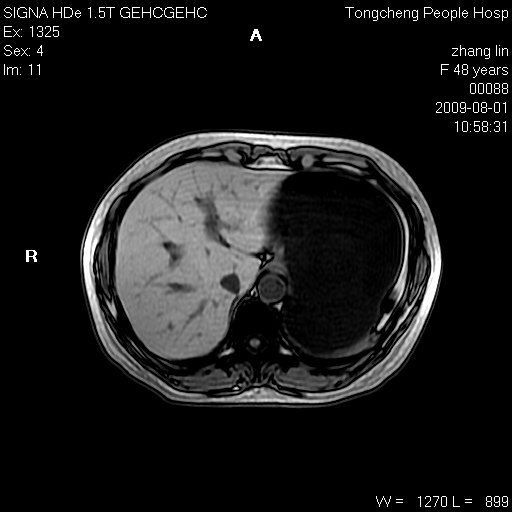

女,48岁。健康体检,彩超发现右肾占位性病变。平素健康。

临床诊断:右肾占位性病变,性质待定(囊肿?肿瘤?)。

上中腹部mr平扫+增强扫描,图像如下:

右肾上极见一类圆形病灶,t1wi呈等信号t2wi呈等高混杂信号,三期增强无强化,边界清---考虑囊肿出血。

肝囊肿